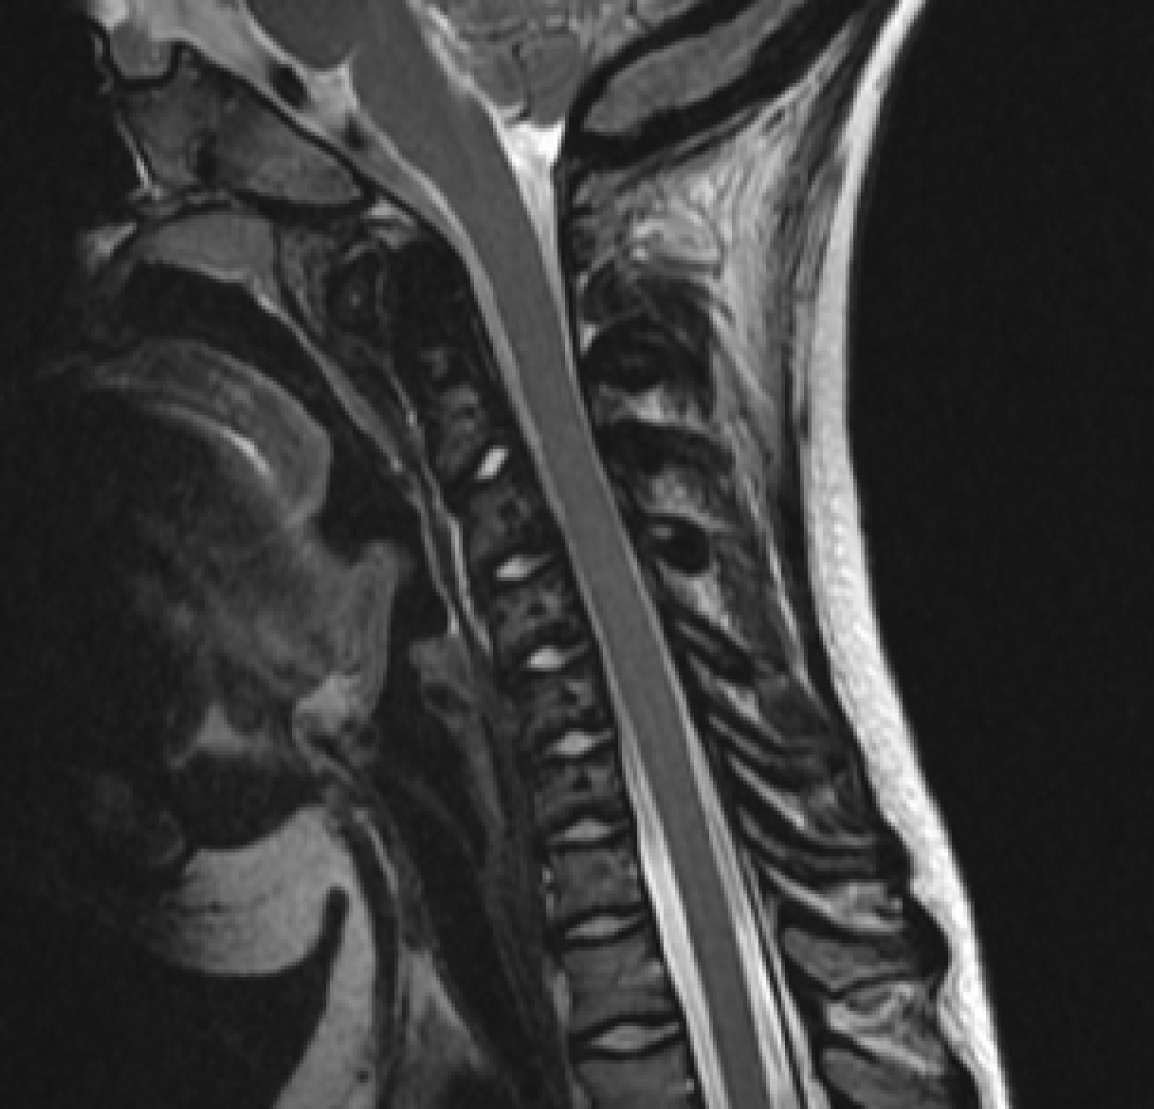

Figure 4

A “sandwich vertebrae” appearance (magnetic resonance imaging T2-weighted images).